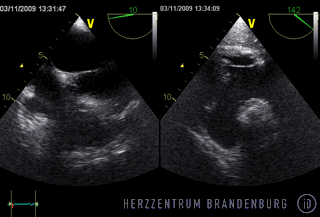

Im Rahmen der Behandlung ist es zunächst wichtig festzustellen wie ausgedehnt eine Infektion fortgeschritten ist. In der Regel ist dazu eine transösophageale Echokardiographie notwendig, um das Ausmaß und die Größe von Vegetationen festzustellen und eine eventuelle Klappenmitbeteiligung einschätzen zu können. Das weitere Vorgehen muss danach individuell, meist in enger Kooperation zwischen interventioneller Kardiologie und Herzchirurgie festgelegt werden.